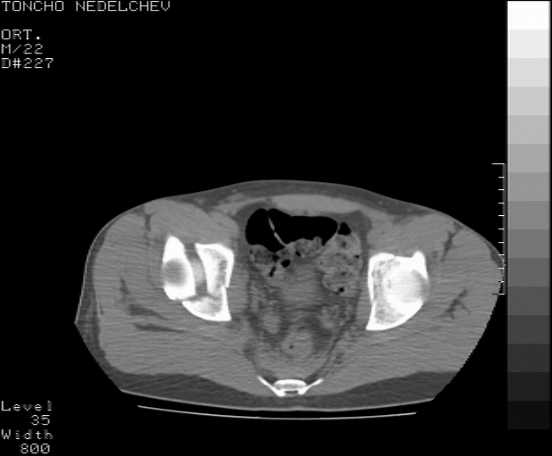

The details of the fracture are not so clear from the images sent...would you be able to send along an AP and Judet images as well as some additional axial images above and below the joint?

I’m not so sure that your patient has a Tr+PW pattern based on the images sent...maybe the fracture’s exact name won’t matter in the long run, but it’d be great to see enough images to make an accurate comment.

Without complete CT images and/or oblique radiographs, it's difficult to answer your question definitively, but it appears that there may not be a posterior wall fracture that requires a posterior approach. A successful reduction through an ilio-inguinal approach will have a faster recovery, and not risk SGN injury or heterotopic ossification.

Here are some more axial images. What is your opinion as for the timing of the operative treatment?

Yordan! In this case position of bone fragments is quite good. We

prefer to use miniinvasive technique. We fix posterior column by can. screw and put 3mm pin with distal thread to the anterior column. Next day after the surgery he may start walking with crutches. 3 month after the surgery we remove the pin. In cases of maleolar fractures we use

angle stable plates to lat. mal. and pins or screws and if syndesmosis is intact - full loading is not forbidden.